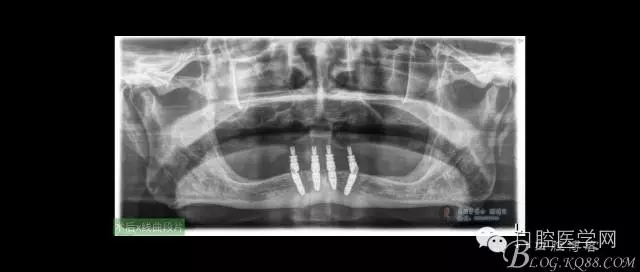

ICX-ON-4即刻負(fù)重